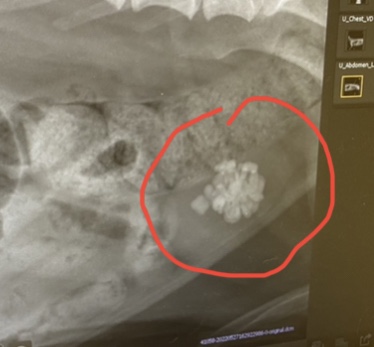

Second – When they took the heart x-ray she notice that he has KIDNEY STONES (arrow above but see closer image below). This was an ‘incidental finding’ since she was actually x-raying his heart. According to pethealthnetwork.com, metabolic kidney stones, those that form due to some blood or urinary imbalance, are a bit more common than those from infection. The most common type is calcium oxalate. There are several different types of stones (we are learning). Stones tend to be a small dog thing but usually females. We are hoping they are not calcium oxalate but actually something called Struvite. That is a composite of magnesium, ammonium, and phosphate and can be dissolved, where the calcium oxalate can’t.